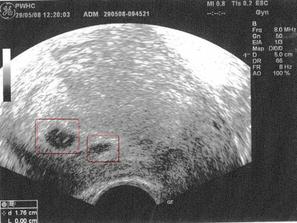

Diky hodne dr. Zelenkove jsem na neplanovanem UTZ videla 29.5.2008, že v sobě nosím 2 gestační váčky. Jeden je trochu menší - snad to nic špatného neznamená. 2.6. další UTZ v Pronatalu, to by mohlo být vidět i srdíčko. Fotku dostal manžel k narozeninám a hned mi ji v práci oscannoval. Pracovní název: Karel a Hyacint (ale nebojte, tyhle jména jim nezůstanou!).

V tehotenství (stejně jako v životě) je to pořád nějaká změna. 2.6. zjistila dr. Slámová v Pronatalu, že se jedno embryo rozdělilo, dostala jsem teda hned tři fotky, ale založili jsme je do hodně hlubokého šuplíku. Hrozí hodně vysoké riziko poškození rozděleného plodu (jednovaječných dvojčat), teď musím ležet a do 12 tt se rozhodne, co bude dál.